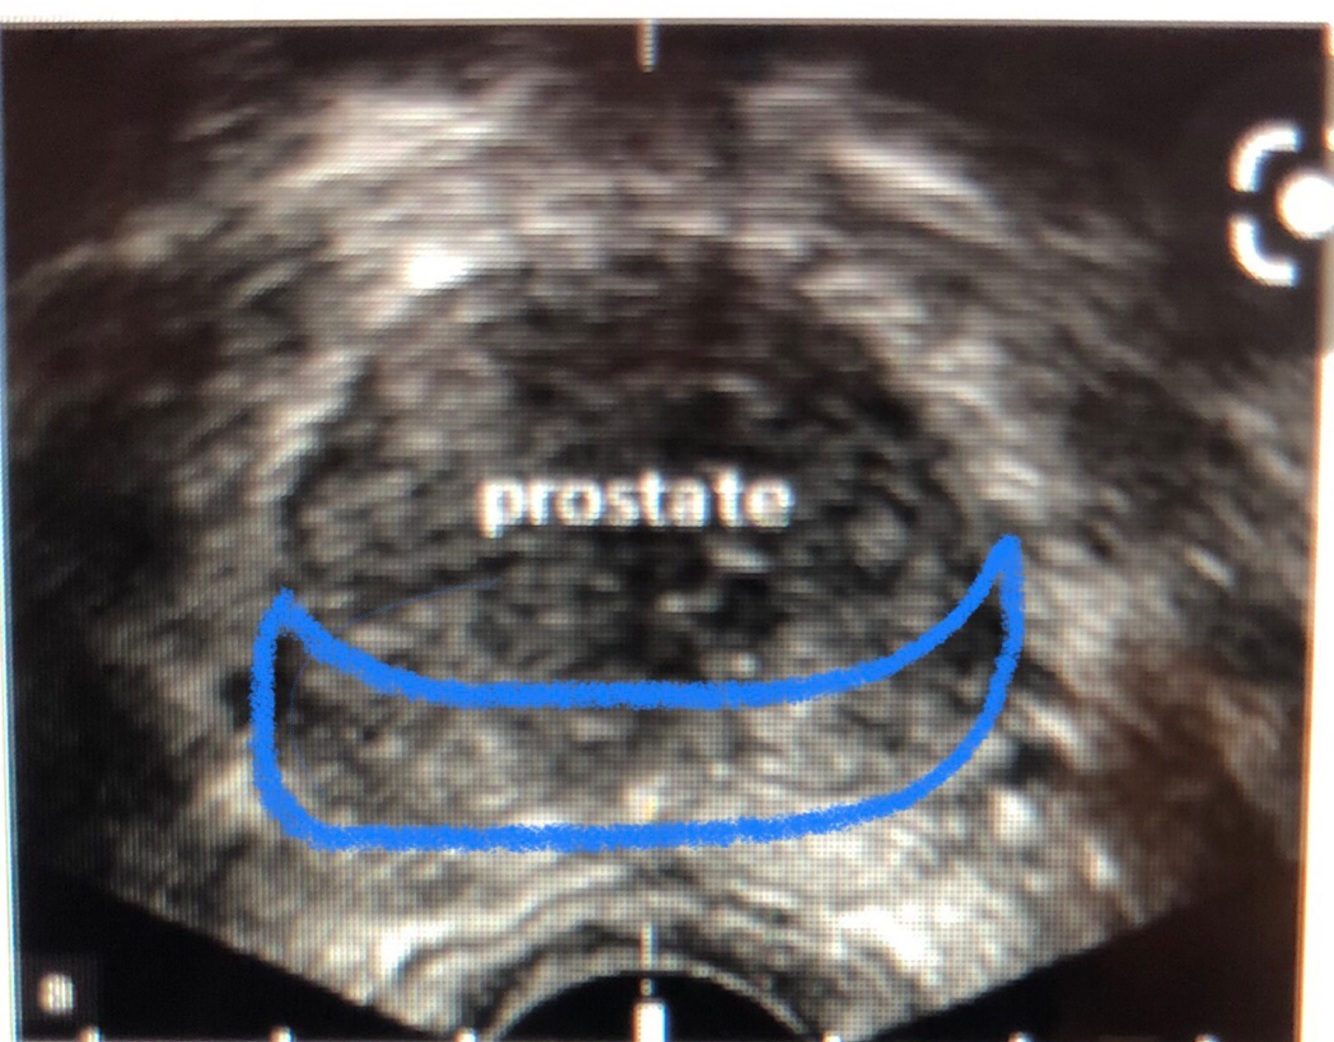

What zone is this

What zone is surrounded by blue

A

Peripheral